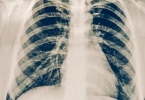

• 肺气肿有效治疗方法

肺气肿有效治疗方法

肺气肿可通过戒烟、药物治疗、氧疗、肺康复训练、手术治疗等方式改善。肺气肿通常由长期吸烟、空气污染、遗传因素、职业粉尘暴露、呼吸道感染等原因引起。1、戒烟:戒烟是肺气肿治疗的首要措施。烟草烟雾中的有害物 ...